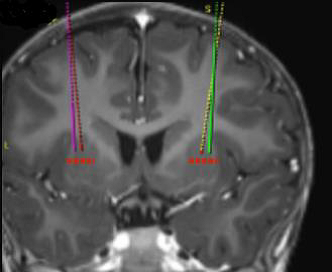

Die angestrebten Infusionsstellen werden gemäß der stereotaktischen neurochirurgischen Standardpraxis definiert. Upstaza wird als eine bilaterale Infusion (2 Infusionen pro Putamen) mit einer intrakraniellen Kanüle verabreicht. Die 4 endgültigen Ziele für jeden Zielkanal sind als 2 mm dorsal zu (über) den vorderen und hinteren Zielpunkten in der mittelhorizontalen Ebene zu definieren (Abbildung 1).

Abbildung 1 Die vier Zielpunkte für die Infusionsstellen